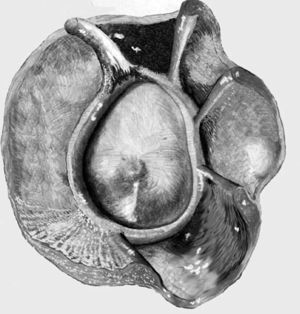

Con el brazo en abducción a 90 grados, el hombro puede realizar una rotación externa, a partir de la horizontal, de aproximadamente 100 a 120 grados, y una rotación interna de aproximadamente 100 a 120 grados, dependiendo del entrenamiento. Durante este movimiento la cabeza humeral tiene su punto de rotación en el centro de la cavidad glenoidea y el trocánter describe un arco centrado en este punto (fig. 5).

Los ligamentos glenohumerales superior, medio e inferior refuerzan la parte anterior de la articulación. El LG es una estructura fibrosa que rodea el borde de la cavidad glenoidea e incrementa la profundidad de la misma, y por lo tanto la estabilidad de la articulación. Asimismo, ayuda a prevenir las fuerzas de traslación, especialmente en la parte inferior de la articulación, donde el labio se halla más firmemente adherido al borde glenoideo, a la cápsula articular y al periostio. De todas formas la función más importante del LG es la de servir de punto de inserción de los ligamentos glenohumerales y del TLB.